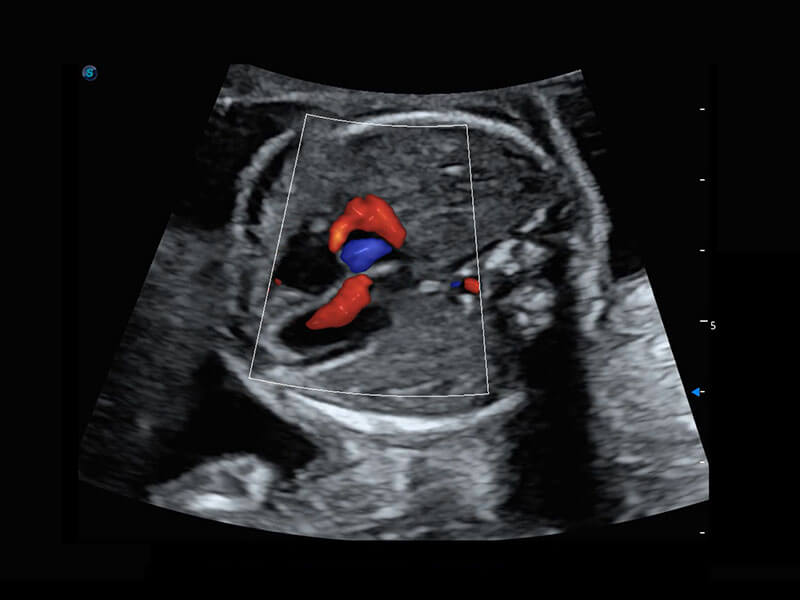

早孕筛查

P60在胎儿早孕期超声筛查中为您带来优异的图像质量。

• 早孕-胎心

• 胎儿体循环